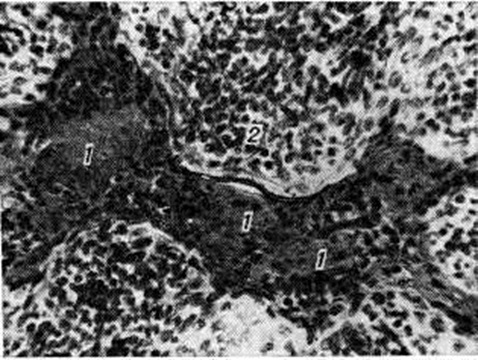

Патологическая анатомия. Морфологически изменения в небных миндалинах при хронический Тонзиллит отличаются большим разнообразием. Наблюдаются десквамации или ороговение эпителия, выраженная инфильтрация его лимфоцитами и полиморфно-ядерными лейкоцитами, которые мигрируют в лакуны (миндаликовые крипты), где образуются плотные пробки (рисунок 1). При этом формируются папиллярные выросты эпителия лакун (рисунок 2), которые способствуют задержке в них патологический содержимого. В подэпителиальном слое отмечается разрастание соединительной ткани. В паренхиме небной миндалины выявляются очаги размягчения лимфоидной ткани (хронический паренхиматозный Тонзиллит) либо массивные разрастания соединительной ткани (хронический паренхиматозный склеротический Тонзиллит). Наряду с инволюцией лимфатических, фолликулов отмечается их гиперплазия с многочисленными митозами в светлых центрах. В псевдокапсуле (миндаликовая капсула) и паратонзиллярной клетчатке чаще всего встречаются склеротические изменения. Отмечается периваскулярный склероз — мелкие и средние артерии окружены муфтообразными разрастаниями соединительной ткани, бедной клеточными элементами. Лимф, сосуды и капилляры деформированы pi частично облитерированы. Признаки постепенного запустевания обнаруживаются и в венах, при этом ретикулярная ткань вокруг них подвергается гиалинозу (смотри полный свод знаний). Периваскулярная инфильтрация сопровождается в одних сосудах запустеванием просвета, в других — ослаблением мышечного тонуса и повышением проницаемости стенок, что приводит к снижению скорости кровотока и способствует застойным явлениям. Нарушение лимфооттока из миндалин ведёт к застойным и воспалительным изменениям в регионарных лимфатических, узлах.

Рис. 1.

Микропрепарат небной миндалины больного хроническим тонзиллитом: 1 — плотные пробки в просвете лакун; 2 — лимфоплазмоцитарный инфильтрат; окраска гематоксилин-эозином; ×400.